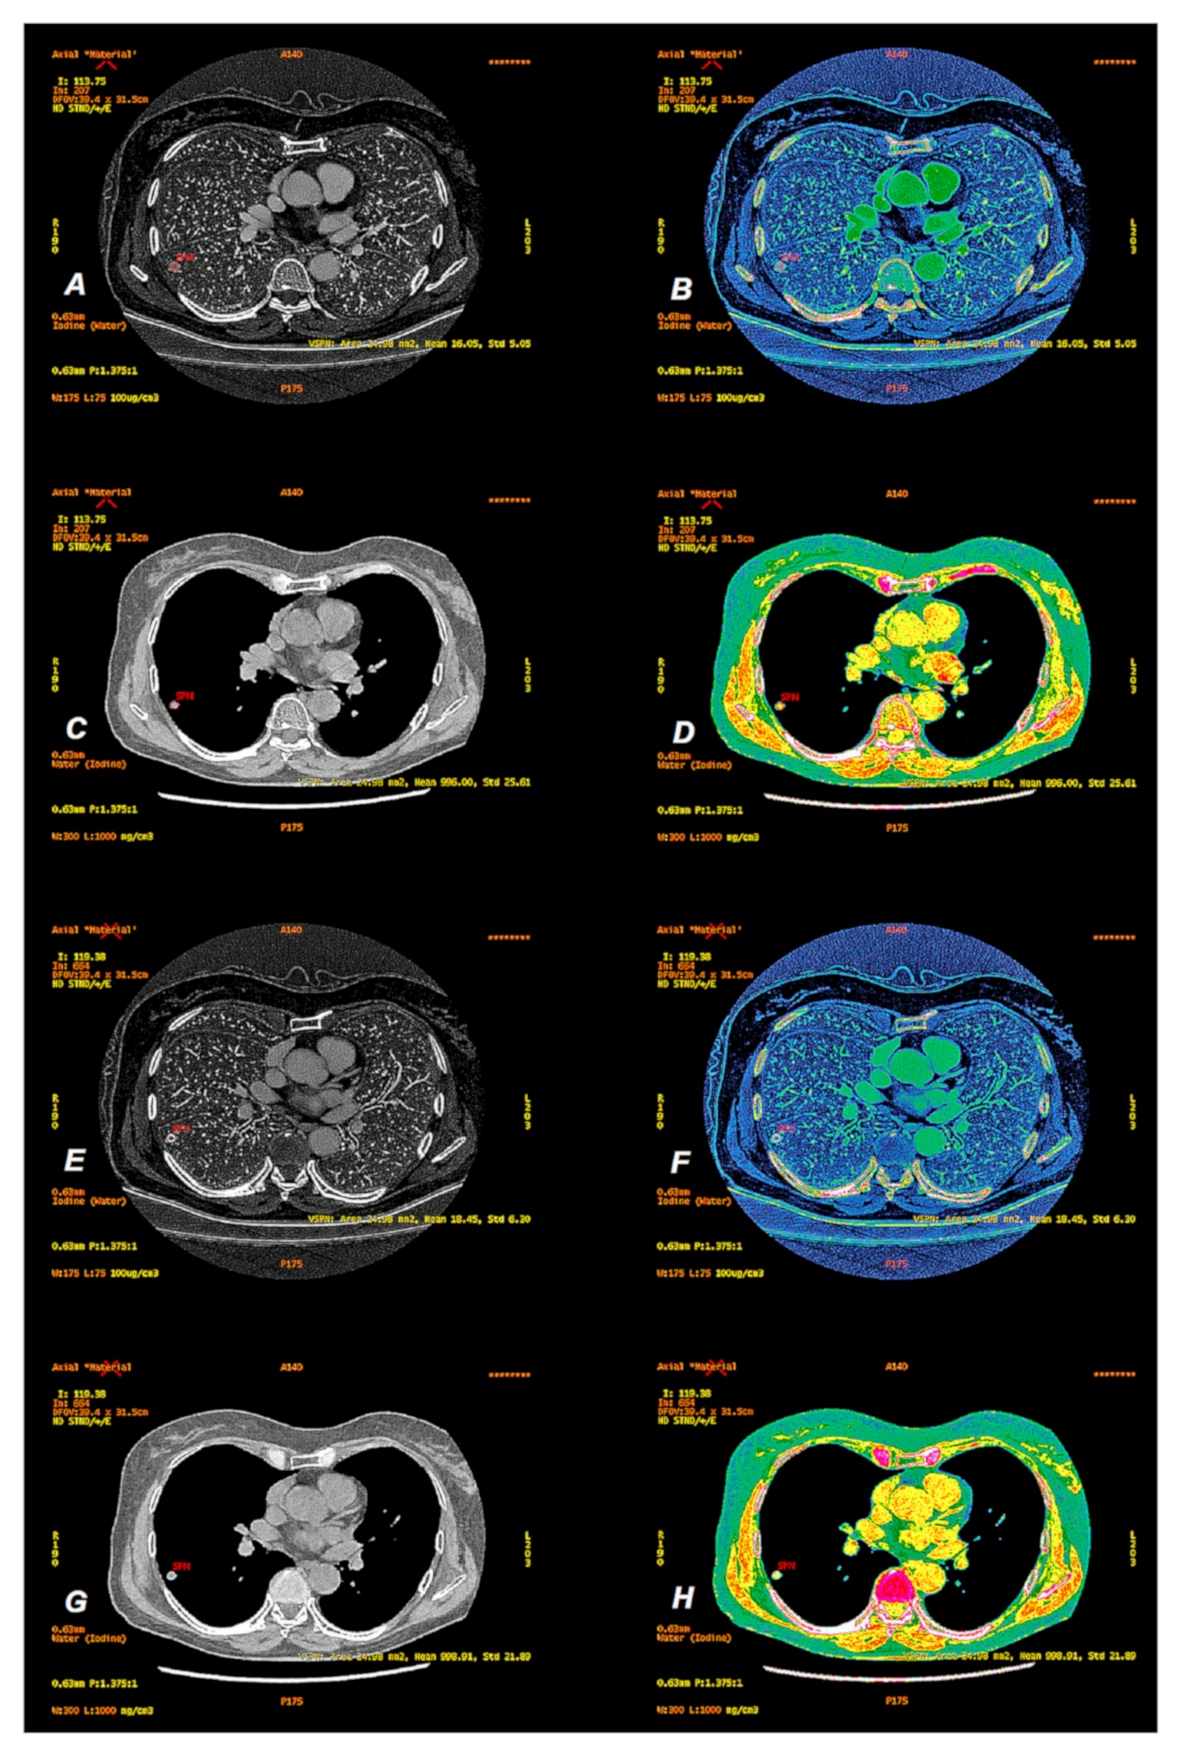

2. Materials and Methods

2.2. CT Scanning Parameters

2.3. Data Analyses

3.1.2. Comparison of Iodine Concentration in IC Maps, Water Concentration (WC) and Radiation Absorption in Lung Tumors in AP and VP of DECT Examination